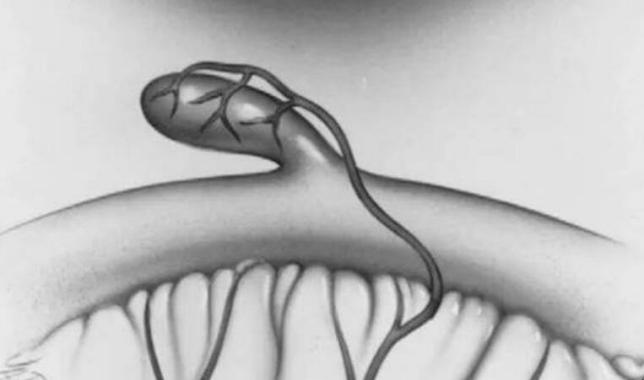

梅克尔憩室(Meckel’s diverticulum),又称先天性回肠末段憩室,由于卵黄管退化不全,其肠端未闭合引起一种先天性肠道畸形,表现为末端回肠的肠系膜附着缘对侧有憩室样突起。正常人群中的发生率为2% ~ 4%,男性多于女性2倍,2岁以内幼儿多见,男性出现并发症也多于女性。

大多数无任何症状,少数可发生并发症如 出血、憩室炎、穿孔、肠梗阻等。 消化道出血时多表现为暗红色血便,肠梗阻时可有腹胀、腹痛,呕吐等不适,憩室炎可出现穿孔诱发弥漫性腹膜炎,严重时可危及生命。 因此家属在发现小孩子便血、腹痛,呕吐等不适时应引起注意,必要时及时就医。